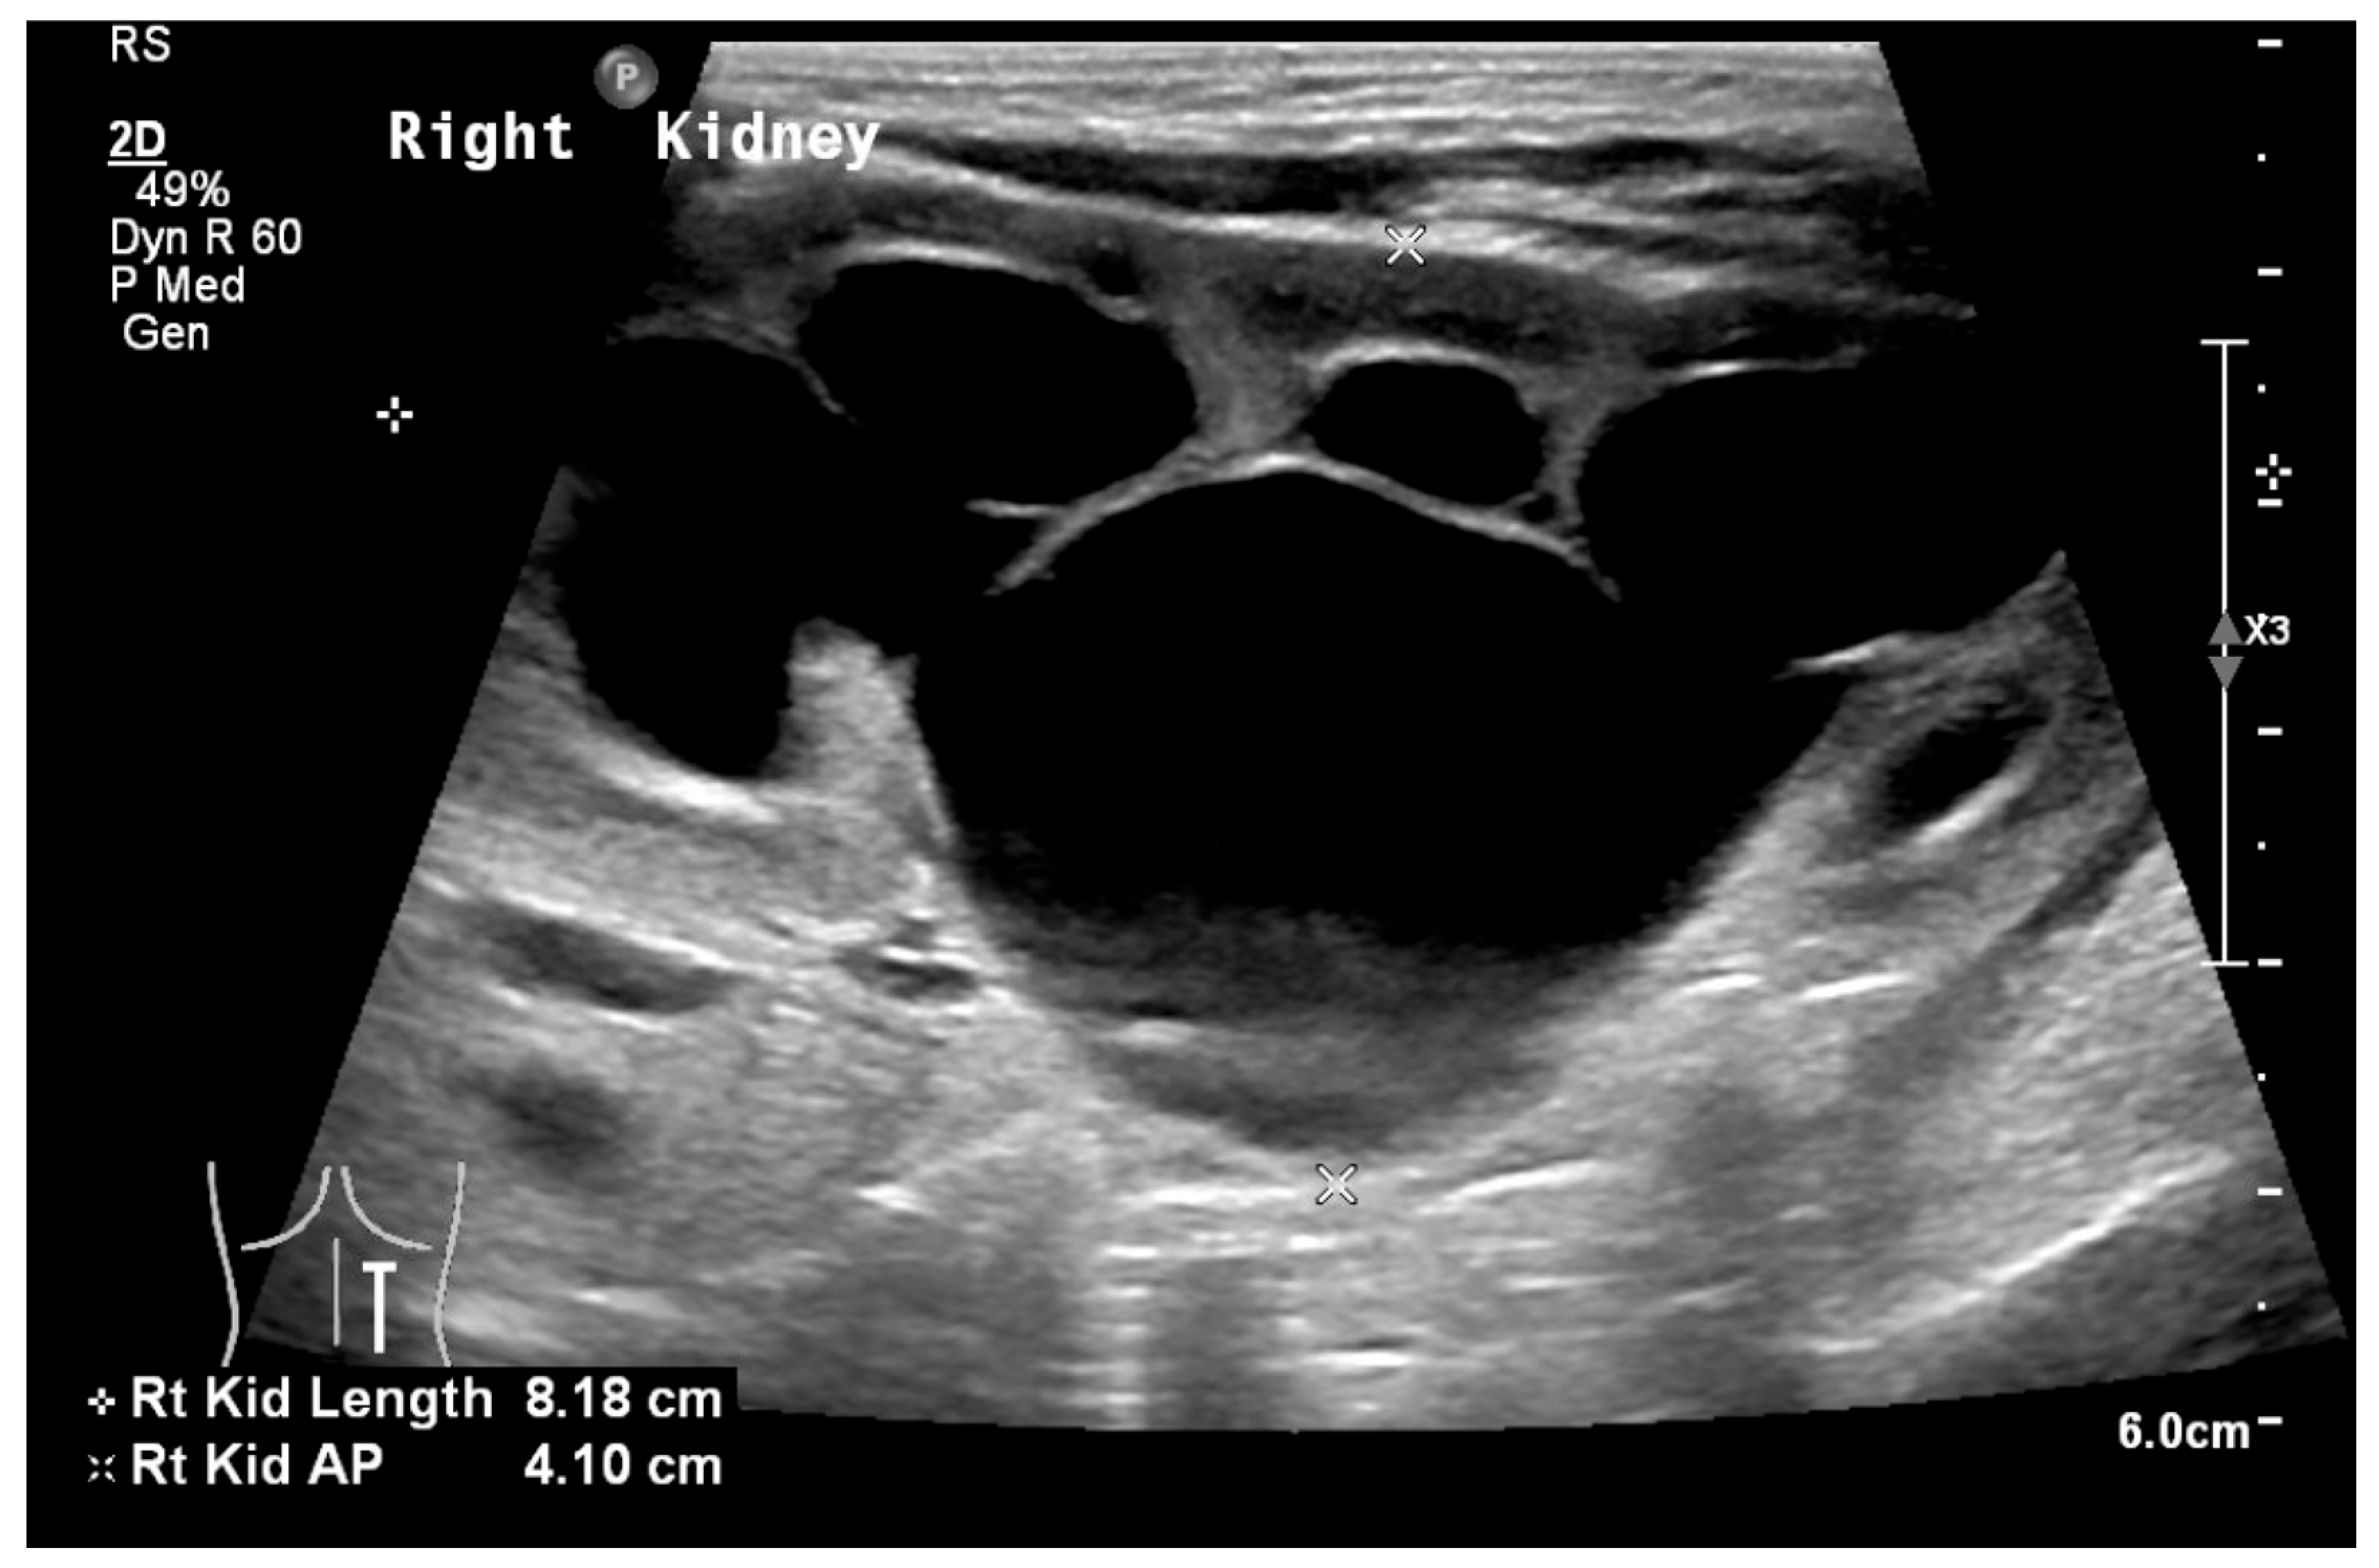

| Grade | Ultrasound Description |

|---|---|

| 0 | No hydronephrosis |

| 1 | Only the renal pelvis is visible |

| 2 | Renal pelvis and a few calyces visible |

| 3 | Virtually all calyces visible |

| 4 | Similar to grade 3, but with parenchymal thinning |